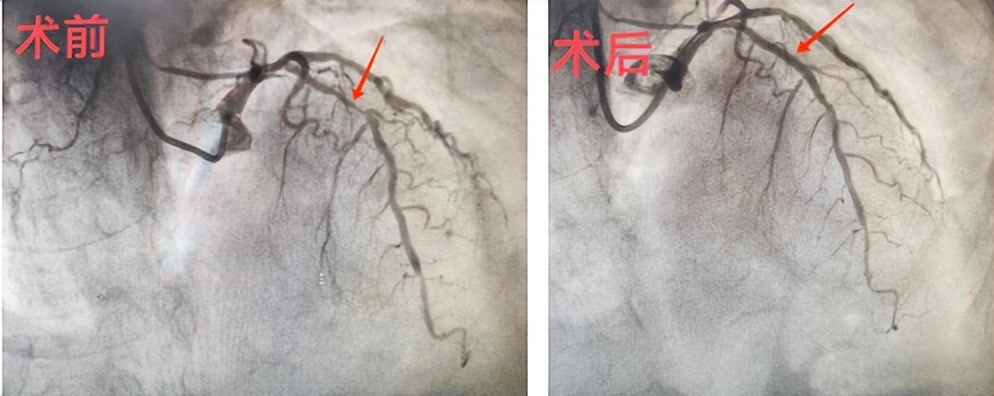

随后,患者在我院介入导管室接受了冠状动脉造影检查。

结果显示,患者LAD(前降支)近段狭窄最重处约90%,远段狭窄约85%,且伴有严重钙化。

吴强主任首先尝试了球囊预扩张并植入支架,但由于支架难以通过病变处,如果血管未被充分预扩张,就无法进行支架植入。考虑到病变处冠脉钙化严重,被动选择冠脉内旋磨术。在钻头旋转速度达到每分钟150,000转的情况下,患者血管内的钙化斑块几十秒钟内被磨开了一条宽敞通畅的“路”。随后,吴强主任成功地给患者完成了支架植入手术。手术顺利完成,术后患者胸闷痛症状明显缓解。